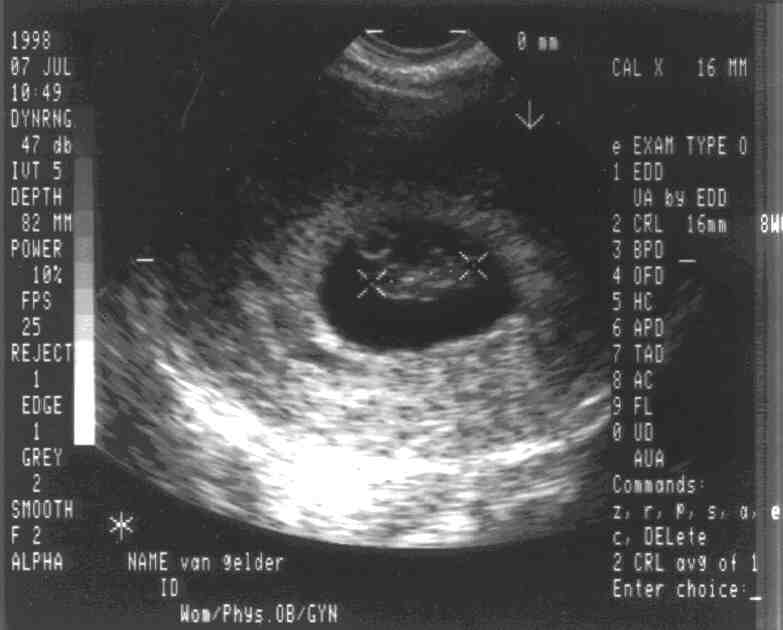

8 weeks length measurement

The two "X" measure the head to end of the spine. On the right column of gibberish, you'll read "CRL 16mm 8W0". That means the measurement is 16mm and that implies peanut is 8 weeks, and 0 days old (as of July 7, 1998). See the other 8 week sonogram for more information on this stage.